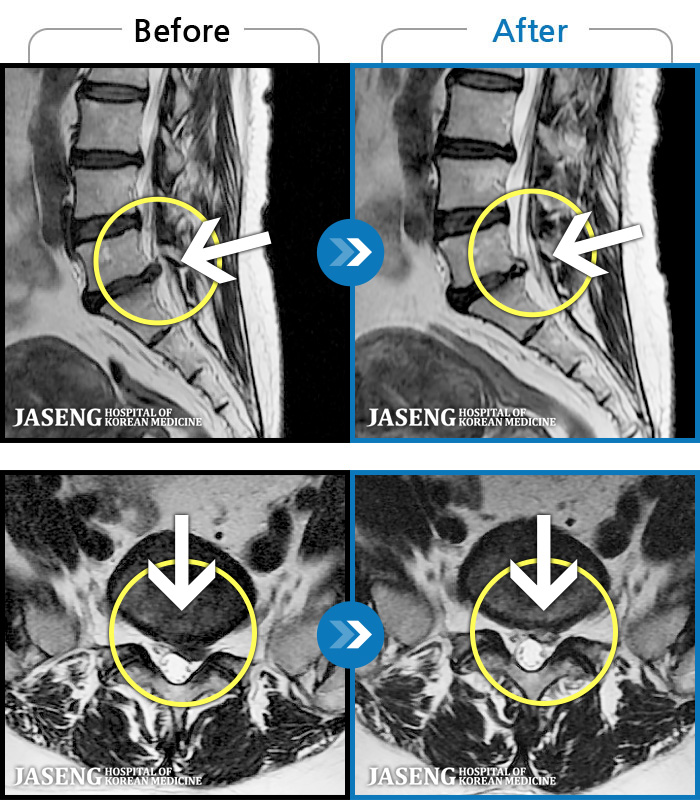

- MRI ġ

MRI ġ

1,301 MRI ũ ʸ Ȯϼ.